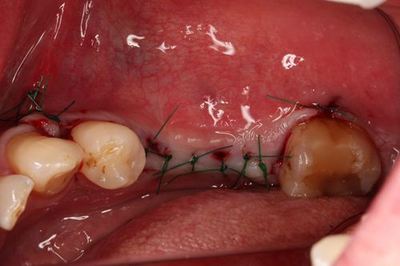

縫合を終えました。

オペ終了時のレントゲン写真です。

約1週間後に抜糸します。

インプラントの埋入トルクが15Ncmを越えていますので

6週間後から咬合できるように準備をします。